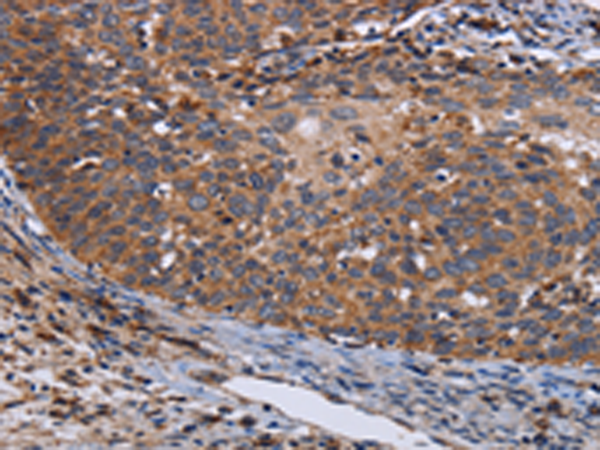

分类: 科研抗体货号: P08522别名: 5c5-2; L12mt; MRPL7; RPML12; MRPL7/L12; MRP-L31/34应用: WB,IHC反应种属: Human, Mouse